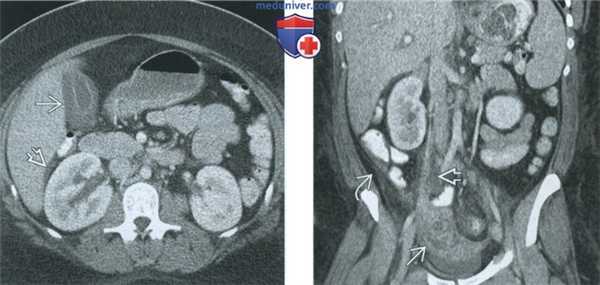

(Слева) При КТ с контрастным усилением в аксиальной плоскости в придатках матки выявляется сложное кистозное образование, имеющее толстую стенку и перегородки, сигнал от которых усиливается при введении контрастного вещества, - картина, соответствующая тубоовариальному абсцессу. Идентифицировать нормальный яичник, расположенный отдельно от маточной трубы, не удается.

(Справа) При КТ с контрастным усилением в корональной плоскости у той же пациентки наиболее отчетливо видны воспалительные изменения вокруг описанного на предыдущем рисунке крупного тубоовариального абсцесса.

(Слева) При КТ с контрастным усилением в аксиальной плоскости у пациентки с тубоовариальным абсцессом выявляется диффузное утолщение стенки желчного пузыря, который имеет нормальные размеры. В гепаторенальном углублении (кармане Моррисона) имеется свободная жидкость.

(Справа) При КТ с контрастным усилением в корональной плоскости у той же пациентки справа виден тубоовариальный абсцесс и воспалительные изменения вдоль сосудистой ножки яичника. В правом боковом канале отмечаются свободная жидкость и тяжистый рисунок. Распространение воспалительного процесса по правому боковому каналу в правый верхний квадрант живота укладывается в картину синдрома Фитц-Хью-Куртиса.